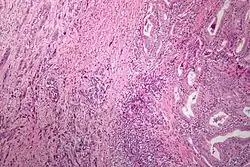

فقد التمايز الخلوي[1] أو التحول الراجع[2] أو الكَشَم[3] هو حالة للخلايا تتميز بفقر التمايز الخلوي، وهي حالة تعرض خاصة في السرطانات.[4]